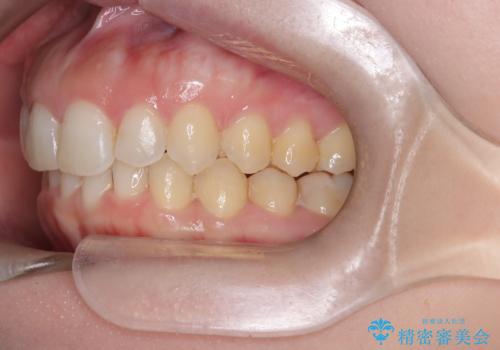

【インビザライン】前歯の凸凹を治したい。

- 前歯の凸凹を主訴に来院されました。

深い噛み合わせも同時に治療を行う計画を立て、インビザラインを使用して歯並びの改善を行うことができました。

叢生改善のために遠心移動とIPRを行なっています。